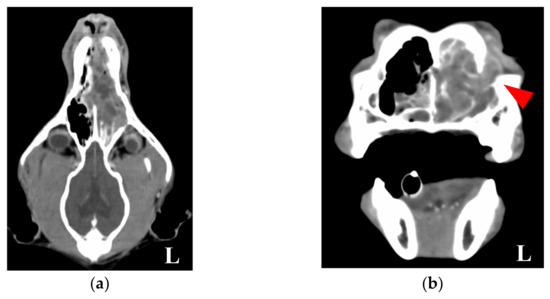

2.1. Case Presentation